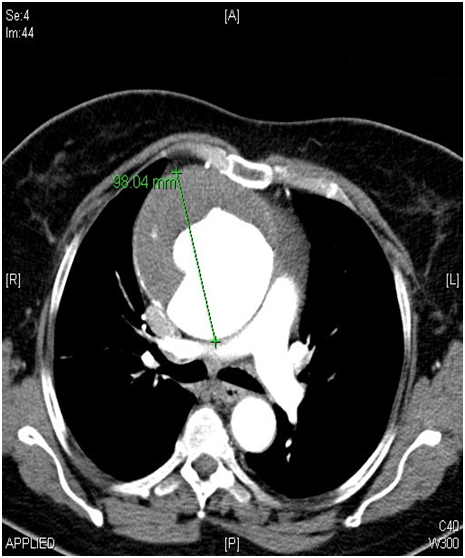

A 62-year-old female patient with known hypertension, obesity history was referred to the cardiology polyclinic by inhalation and diuretic therapy after examination of her chest diseases polyclinic with shortness of breath and rapid fatigue. Blood pressure was measured 130/80 mmHg in both of arm, pulse was 114/m and irregular. Periferal pulses were fuller, faster, arrhtymic on all extremity. Heart sounds were heard as a 3/6 diastolic murmur in aortic focus and 2/6 systolic murmur in mitral focus. Respiratory sounds were normal and equal in both of hemithorax. Hyperlipidemia, impaired fasting glucose, normal renal function were detected in laboratory tests. In echocardiographic examination was revealed ejection fraction %32, mild mitral and tricuspid regurgitation, modarete aortic regurgitation and degeneration at both of valves, aneurismatic dilatation in ascending aorta (9.1 cm) and aortic arch (5.4 cm) were revealed (Figure 1). There was seen dissection fleb in proximal ascending aorta and thrombus was observed in false lumen. Afterwards, that patient was scaned by thoracoabdominal computerized tomography angiography. Diameter of aneursym was measured 9.8 cm and it was extending to the arch aorta (Figure 2 & 3). Dissection and plaque were not seen on carotid doppler ultrasonography. Coronary angiography was not applied to patient before surgery operation because of high risk. Supracoronary Graft Interposition and Hemiarchus Replacement was applied to patient after preparations were completed (Figure 4 & 5). Prostetic aortic valve replacment was not performed to patient because of there was no pathology other than degeneration. Control echocardiography was performed after intensive care process. Ejection fraction was measured %55 and seen mild mitral-aortic-tricuspid regurgitation. The patient was discharged after 6 days without any problems in the postoperative period.

Figure 2: Computerized Tomography Angiography Image of Ascending Aort Aneursym with chronic dissection.

Figure 3: Computerized Tomography Angiography Image of Ascending Aort Aneursym with chronic dissection.

Even though abdominal aortic aneursym is seen the most frequently, thoracic aortic aneursym have different importance because of it is quite as development of rupture and dissection clinic. Early diagnosis and treatment prevent from mortality. In the recently published European Cardiology Society Guide to Aortic Diseases (2014) surgical borders are as follows; 45 mm in patients with Marfan's syndrome, 50 mm in patients with bicuspid aortic valve and 55 mm in the other patient group [4]. In our patient, the diameter of ascending aorta was measured as 98 mm in the widest place. Thoracic CT angiography provides us with the most accurate results in terms of assessing how far and where the aneurysm has been measured and how far it has been measured, even though echocardiography is required routine evaluation in outpatient. We also want to emphasize the importance of multimodality imaging in this case.